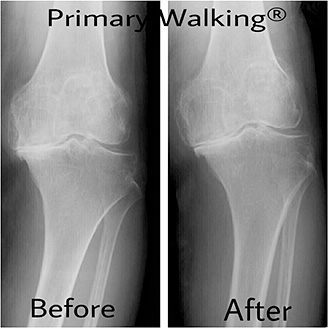

私は娘の猫背にずっと悩んでいました。そんな時に出会ったのが知人に紹介して頂いた岡本先生でした。岡本先生の治療を受けるまでの娘は常に姿勢が悪く毎日私が「姿勢」と注意してもその時は良くなるのですがまたすぐ猫背に戻るの繰り返しでした。初めて先生の所へ治療に行った第一声が「猫背は治ります何回か通院して頂いて施術の立ち方、歩き方を教えるのでそれを実践していったら必ず治りますよ」とおっしゃいました。それから通院しプライマリーウォーキングRの立ち方歩き方を教えて頂き娘も常に意識し頑張っていました。二週間三週間たつにつれどんどん姿勢が良くなっていったのです。施術の立ち方歩き方でこんなに猫背が改善されるだなんて信じられませんでした。それから体、顔周りもスッキリしたのです。姿勢がよくなった事に娘も私も大喜びでした。本当に先生に教えて頂き感謝しております。ありがとうございました。